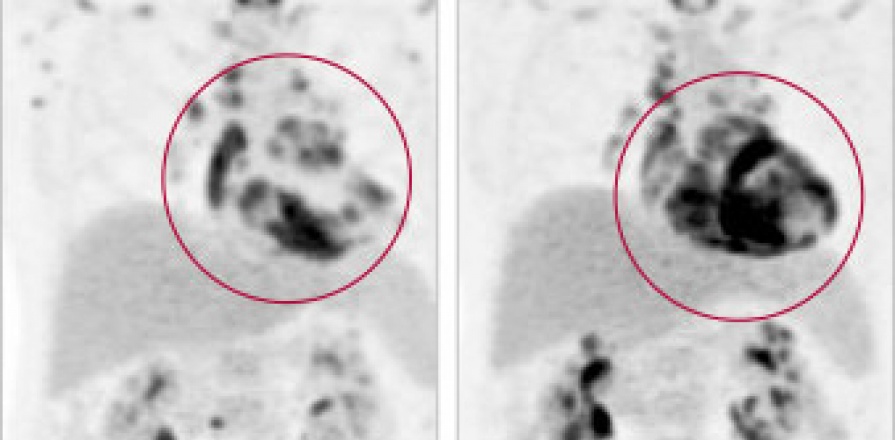

26 juin 2017 Pour un diagnostic exact : Pourquoi les cardiologues doivent penser à la sarcoïdose cardiaque